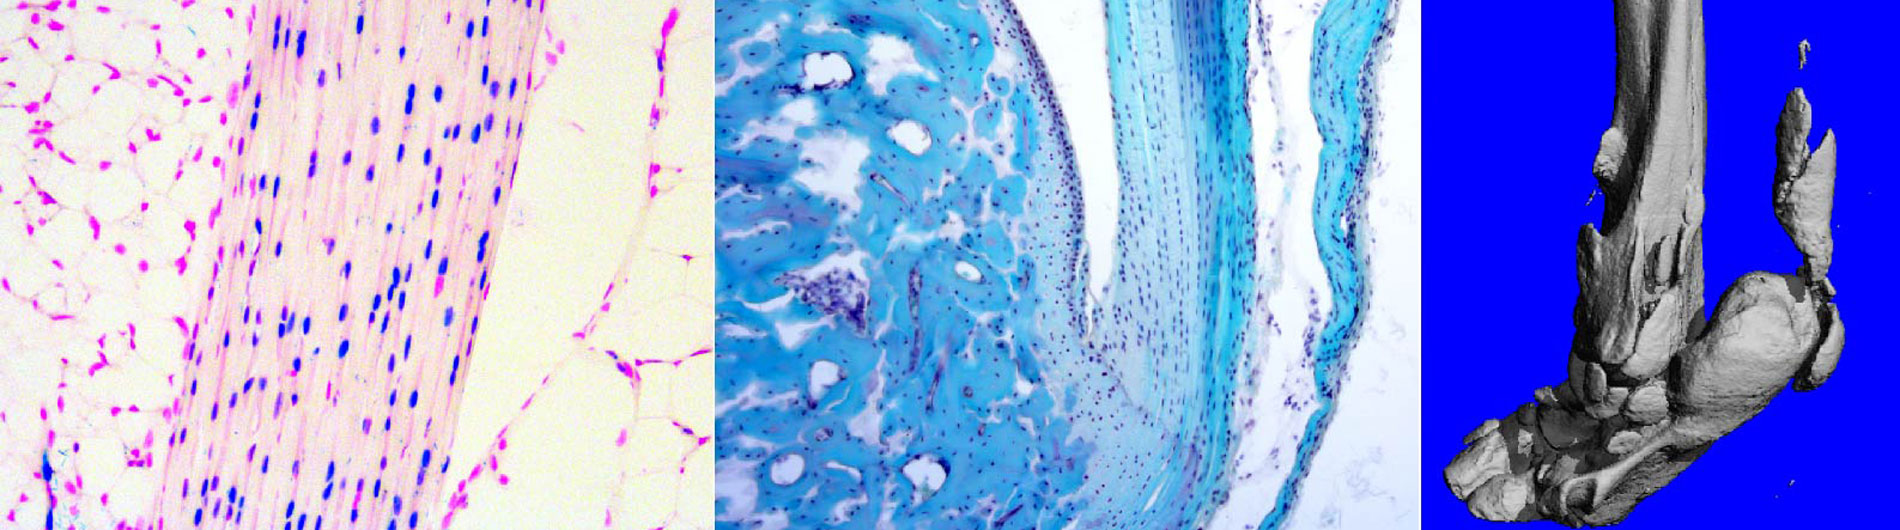

The primary interest of the Cao Laboratory is to understand the physiological and pathophysiological contribution of CaV1.2 Ca2+ channel, its activation mechanisms and the molecular basis of Ca2+-dependent cellular processes during non-excitable musculoskeletal tissue (such as bone and tendon) development, postnatal growth and their repair/regeneration upon injury. Our long-term goal aims to translate our findings related to Ca2+ channel and Ca2+ signaling in basic bone and tendon biology to clinical trials in patients to help prevent and treat musculoskeletal diseases such as osteoporosis, tendinopathies, and heterotopic ossification in soft tissues. We utilize genetic mouse models, primary cell culture systems, pharmacological approaches, next-generation sequencing techniques, multiphoton Ca2+ imaging to define the molecular mechanisms and signaling cascades up/downstream of CaV1.2 in bone and tendon formation.